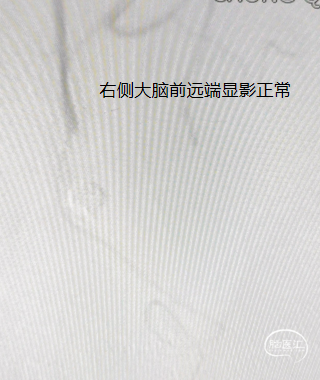

患者右侧大脑前发育纤细;后循环血管无明显异常。

造影见对侧大脑前显影稍差,考虑瘤颈处血栓形成;遂给予静脉团注10ml替罗非班(0.05mg/ml),同时以5ml/h静脉泵注。

造影见对侧大脑前血流恢复,远端瘤体已致密栓塞,但近端瘤体存在残留;